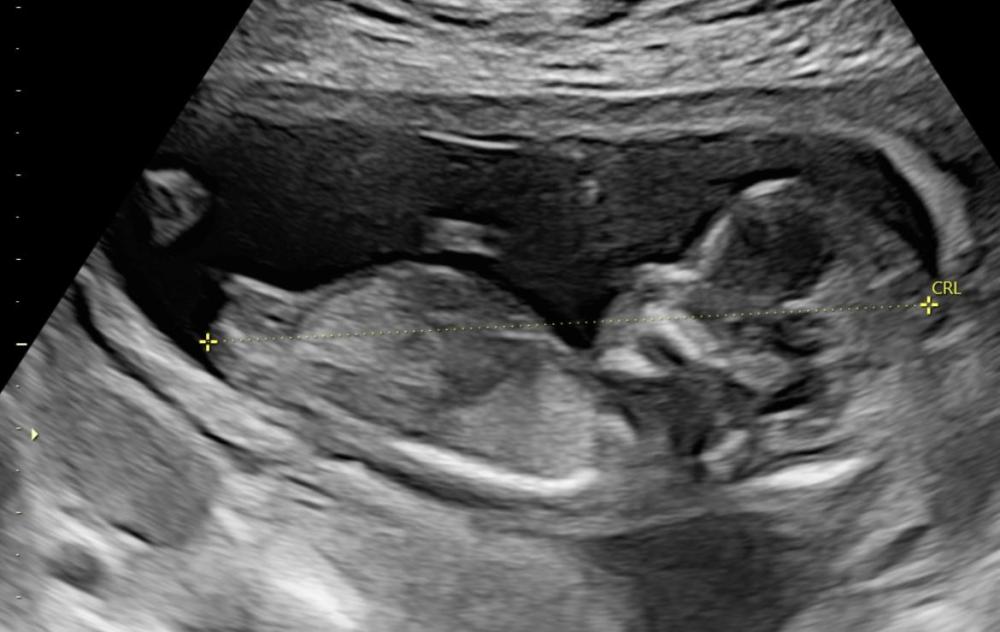

AnonymBruker Skrevet 17. desember 2025 #1 Skrevet 17. desember 2025 Var hos privat jordmor 14+2 og hun sa at vi får en jente, og at hadde det vært gutt hadde vi sett tegn til det nå. Hun mente det var Ingen tvil. Ble veldig glad og vi har begynt å kjøpe inn litt til jente og fortalt alle at det blir jente. I går så leste jeg at det er for tidlig å se kjønn 14+2 og så ble jeg så klart veldig stresset... Er det noen som vet? Kan dette endre seg til gutt? Legger ved ultralydbildet vårt ❤️ Anonymkode: 42a6a...029

AnonymBruker Skrevet 17. desember 2025 #5 Skrevet 17. desember 2025 Dette ser man tydelig er jente fordi det er helt flatt der en penis skulle vært om det hadde vært gutt. Penis ser man fra den vinkelen så sent som 14+2, og den bygger i høyden. Slå deg til ro med at det er jente Anonymkode: 9b3c8...148 1 2

AnonymBruker Skrevet 17. desember 2025 #14 Skrevet 17. desember 2025 AnonymBruker skrev (12 minutter siden): Hvordan kan folk si at det der er bombesikkert? Jeg hadde et nesten nøyaktig likt bilde som ts, legen trodde det var jente - men ut kom verdens skjønneste gutt. Og jeg var i uke 14. Så det er ikke sikkert så tidlig. Anonymkode: c5046...a40 Som jeg skrev over ville en penis vært godt synlig fra akkurat denne vinkelen, da den bygger i høyden som er synlig i profil. Får ikke gjemt en penis i den vinkelen der. Området det er penis skulle vært er godt synlig på bildet, og er helt flatt som er ensbetydende med jente. Blæra ligger også tett under kjønnsorganet slik det ofte gjør hos jenter. Penis (begynnende) er ofte synlig allerede fra uke 12, og vil ikke begynne å utvikles så sent som 14+2 som trådstarter er. Her ser man relativt fullutviklet kvinnelig kjønnsorgan fordi man har vært heldig med vinkel 😊 Tok de såkalt "potty shot" også? Anonymkode: 9b3c8...148 1 1